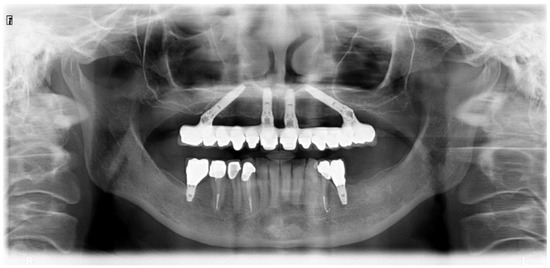

All patients were evaluated clinically up to 7 years and radiographically at 1-, 3- and 5 years. The pretreatment orthopantomography is presented in Figure 2.

Figure 2. Pretreatment orthopantomography.